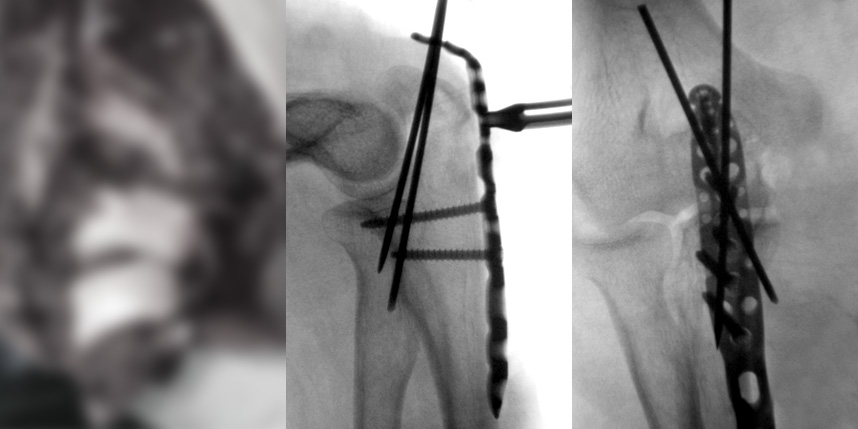

손가락 골절